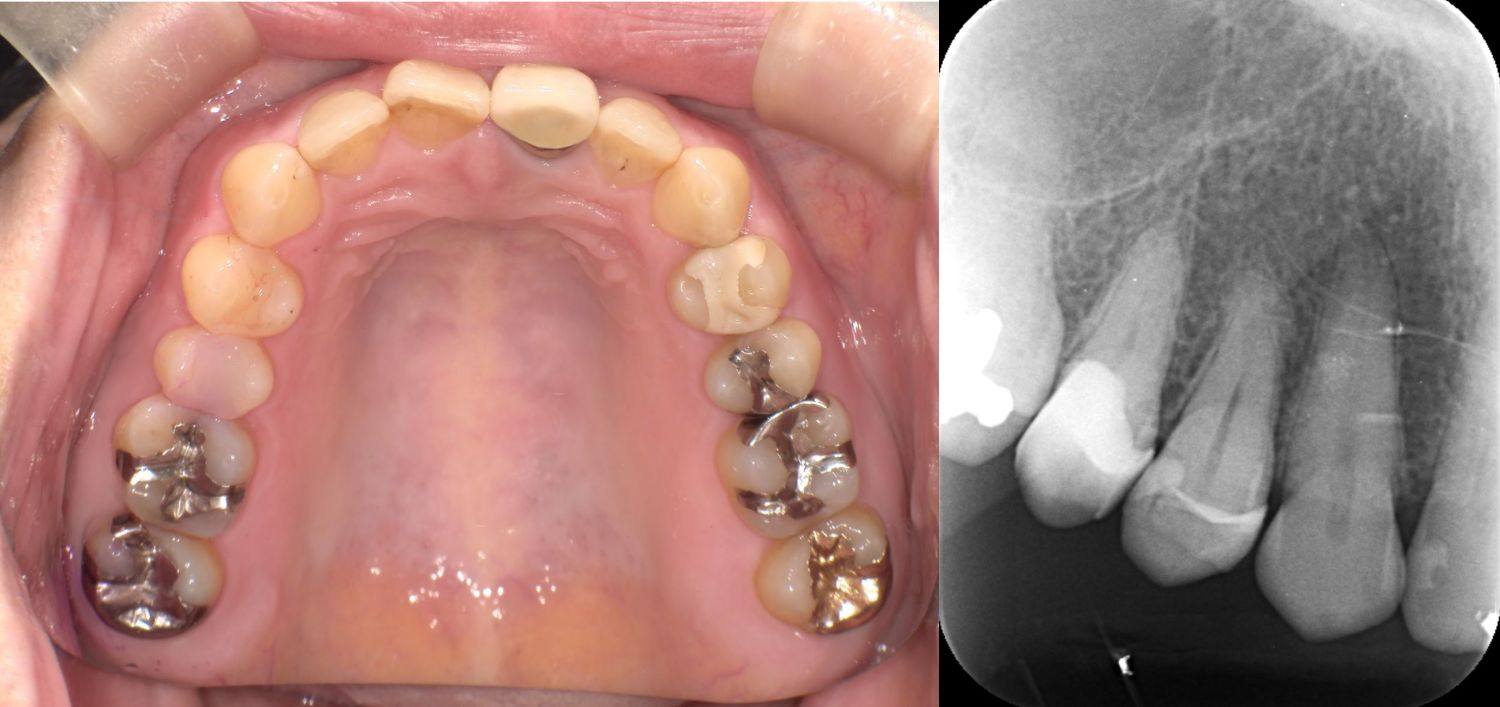

2025/04/22 セレック

OS1457様

通院時年齢 41歳

性別 女性

通院目的 虫歯が気になる

診断 ①右上4う蝕

②左上67う蝕

③左下67う蝕

処置内容 (または主訴) ①セレックインレー

②右上6セレックインレー

右上7CR

③セレックインレー

通院期間 ①~③ 3回(2か月)

費用

①セレックインレー 77,000円

82,500円

③セレックインレー 286,000円

リスク・副作用

研磨や調整が難しく定期的なメンテナンスが必要になることがある、自由診療となるため費用が高額となる

ジルコニアに比べ天然歯に近い分、破折のリスクがある

かみ合わせの変化により適宜調整を必要とする

知覚過敏の出現の可能性がある